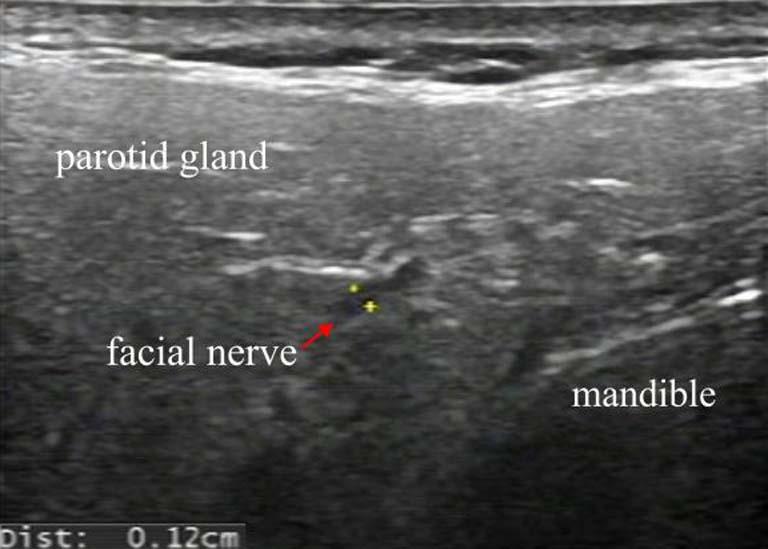

目的 通过高频超声(HFUS)探讨周围性面瘫(PFP)急性期患者颅外段面神经主干直径、局部血流动力学、面肌厚度的改变。 方法 纳入60例急性PFP患者作为PFP组,另纳入30例健康人群作为对照组。通过HFUS扫查并记录颅外段面神经主干直径(FN-d),面动脉直径(FA-d),面动脉收缩期流速(FA-Vs)、面动脉舒张期流速(FA-Vd)、面动脉阻力指数(FA-RI)、额肌厚度(FM-t)、降口角肌厚度(DAO-t)、降口唇肌厚度(DLI-t)等面部参数。评估各面部参数在PFP急性期诊断中的可行性,并进行组内及组间差异性比较,通过Pearson相关性分析PFP患者急性期面部参数与House-Brackmann(H-B)量表评分的相关性。 结果 (1)PFP组H-B量表评分显著低于对照组,差异有统计学意义(P < 0.05)。(2)不同检测者重复测量面部参数可信度良好(ICC > 0.75)。(3)PFP组患侧FN-d、FA-RI值高于健侧和对照组、FA-Vs、FA-Vd、DAO-t、DLI-t值低于健侧和对照组,差异有统计学意义(P < 0.05)。(4)PFP组患侧FN-d、FA-RI值与H-S量表评分成负相关(r = -0.847,P < 0.05;r = -0.863,P < 0.05);FA-Vs、FA-Vd、DAO-t、DLI-t与H-S量表评分成正相关(r = 0.808,P < 0.05;r = 0.757,P < 0.05;r = 0.836,P < 0.05;r = 0.694,P < 0.05)。 结论 HFUS可有效检出PFP患者急性期颅外段面神经主干直径的增加、局部微循环障碍以及面肌萎缩等特征性改变,且FN-d、FA-Vs、FA-Vd、FA-RI、DAO-t、DLI-t的增高与减低能够准确反映PFP的改善或进展,对临床病情监测和疗效评估具有重要的指导意义。

Objective To investigate the changes of diameter of the main trunk of the extracranial segment of the facial nerve, local hemodynamics and facial muscle thickness in patients with peripheral facial palsy (PFP) at acute stage by high frequency ultrasound(HFUS). Methods Sixty patients with acute PFP were enrolled as the PFP group, and 30 healthy people were selected as the control group.The following facial parameters were scanned and recorded using HFUS: diameter of the main trunk of the extracranial segment of the facial nerve (FN-d), facial artery diameter (FA-d), facial artery systolic velocity (FA-Vs), facial artery diastolic velocity (FA-Vd), facial artery resistance index (FA-RI), frontalis muscle thickness (FM-t), depressor anguli oris muscle thickness (DAO-t), and depressor labii inferioris muscle thickness (DLI-t).The feasibility of facial parameters in the diagnosis of acute-phase peripheral facial palsy (PFP) was evaluated, with intra-group and inter-group variability comparisons performed. Pearson correlation analysis was conducted to evaluate the relationship between acute-phase facial parameters and House-Brackmann (H-B) scale scores in PFP patients. Results (1)The H-B score of the PFP group was significantly lower than that of the control group, and the difference was statistically significant (P < 0.05). (2)The reliability of repeated measurements of facial parameters by different testers is good (ICC > 0.75). (3)The FN-d and FA-RI values on the affected side of PFP group were higher than those on the healthy side and control group, and FA-Vs, FA-Vd, DAO-t and DLI-t values were lower than those on the healthy side and control group, with statistical significance (P < 0.05). (4)The FN-d and FA-RI values of the affected side in the PFP group were negatively correlated with the H-S scale score (r = -0.847, P < 0.05; r = -0.863, P < 0.05); FA Vs, FA Vd, DAO-t, DLI-t are positively correlated with H-S scale scores (r = 0.808, P < 0.05; r = 0.757, P < 0.05; r = 0.836, P < 0.05; r = 0.694, P < 0.05). Conclusions HFUS can effectively detect the characteristic changes such as the increase in the diameter of the extrcranial facial nerve trunk, local microcirculation disturbance and facial muscle atrophy in patients with PFP in the acute stage, and the increase and decrease of FN-d, FA Vs, FA Vd, FA-RI, DAO-t, and DLI-t can accurately reflect the improvement or progress of PFP, which has important guiding significance for clinical disease monitoring and efficacy evaluation.